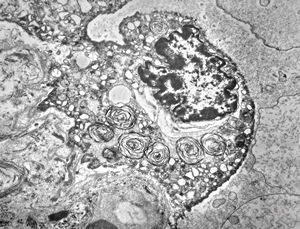

M,50y. | Pneumocystis carinii - lung